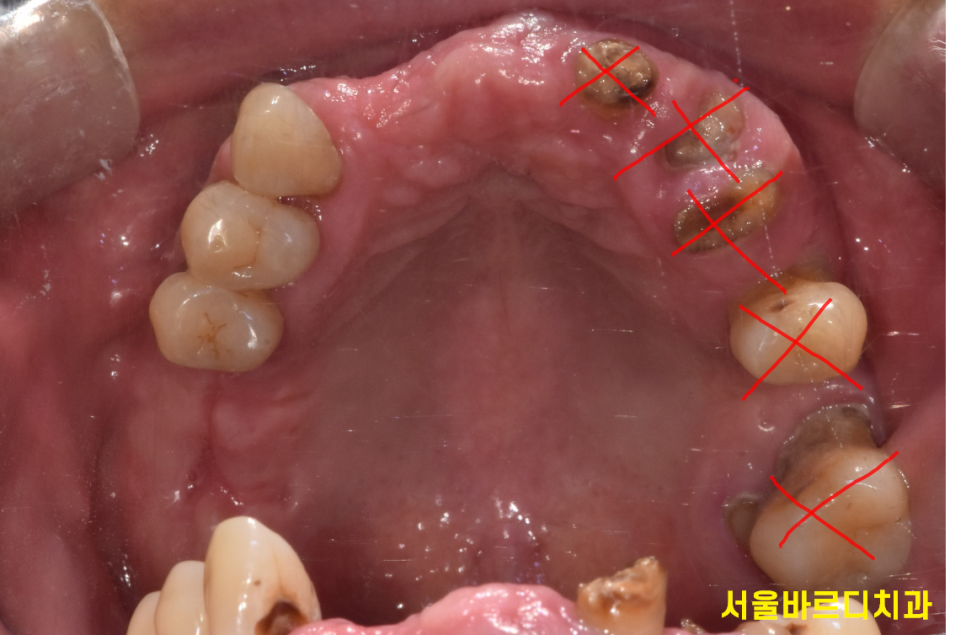

치아를 살릴지 뽑아야할지

임플란트 말고 다른 방안이 있는지 분석하는 것은

치과의사의 영역이니까요...

step 2. 치료 계획 수립

수많은 검사를 통해 어떻게 치료할지

초안이 나오게됩니다.

x ray를 추가적으로 찍게 되고

치아를 흔들어보기도 하며

탕탕 타진해보면서 반응을 살피기도 하죠.